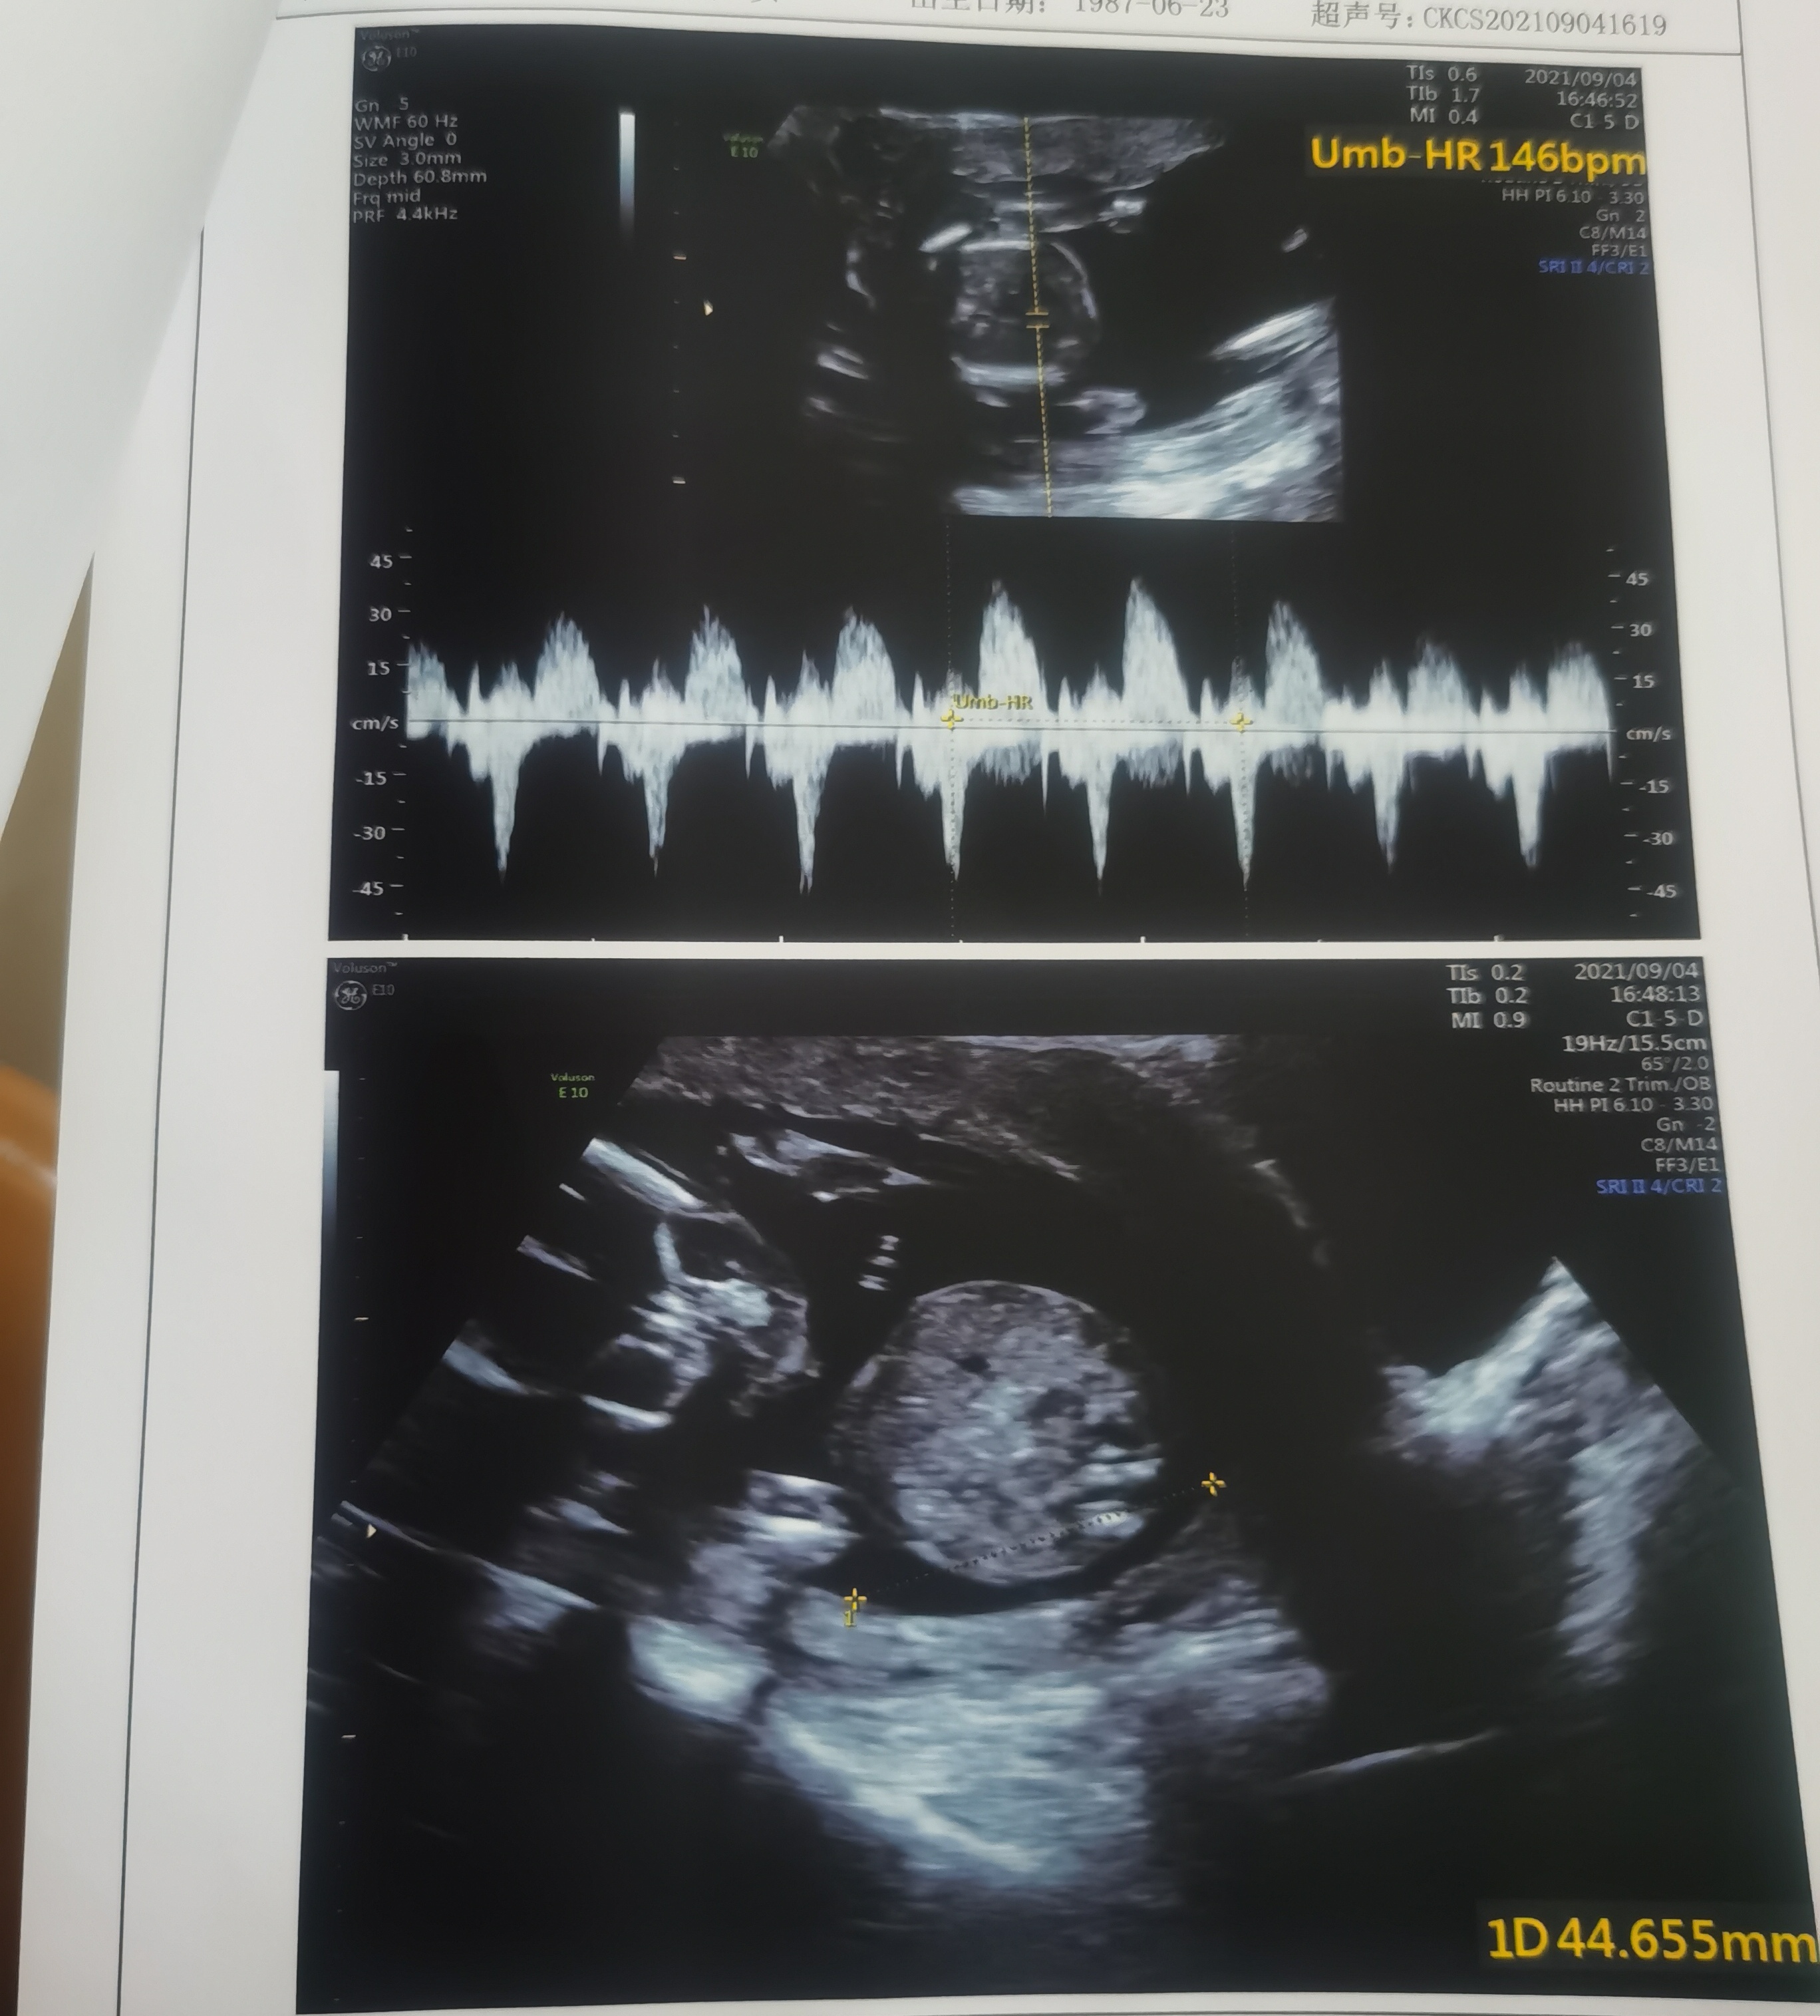

今天是怀孕16周去做了胎心监测还有做了一个B

正常的胎盘附着于子宫体部的前壁、后壁或侧壁,远离宫颈内口。妊娠28周后,胎盘仍附着于子宫下段,其下缘达到或覆盖宫颈内口,位置低于胎儿先露部,称为前置胎盘。你的情况,现在孕周还小,还不能确定是前置胎盘。遵医嘱用药吧!注意休息,观察是否有阴道流血,如果有阴道流血,及时去医院。